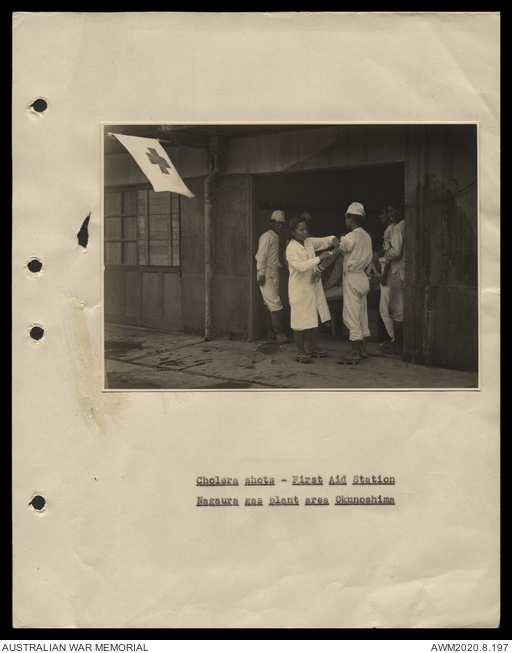

AWM27 501/01 - [Chemical Warfare:] Disposal Report, Chemical Munitions - Operation Lewisite, BCOF Occupation Zone, Japan, 8 May - 30 Nov 1946 [Includes photographs and diagrams]